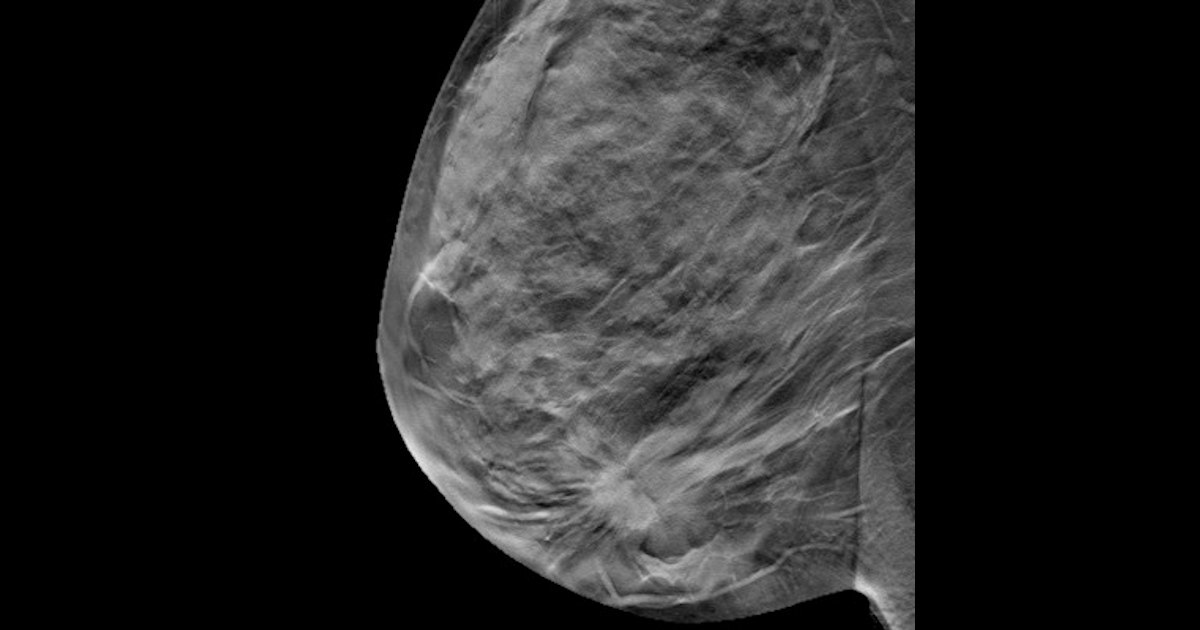

"Female orthopedic surgeons have up to a three times higher rate of breast cancer," Ramsey said in a statement released by BAT manufacturer Burlington Medical Supplies. "Women now make up 55% of medical school attendees and this product was developed with women in mind. BAT reduces radiation to the upper outer quadrant of the breast by over 97%, as well as decreasing exposure to the thyroid, chest, and spine.”